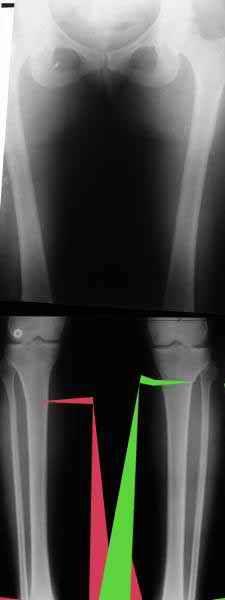

a> Из приведнной схемы не совсеим понял что означают разноцветные линии.

Черные - это нынешняя механическая ось. Красные - это планируемая правильная ось.

a> И зачем латерализация периферического фрагмента.

Медиализация - это чисто эстетический прием, как я понимаю. Поскольку если делать остеотомию ниже вершины деформации, для восстановления оси надо делать смещение по ширине, в данном случае как раз латерализацию.

А вот на схемке без осей - там на разных уровнях (который правильнее?) устранение варуса чисто открытым клином без медиализации-латерализации. Если как-то так сделать - этого недостаточно будет?